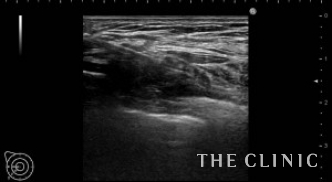

吸引除去した脂肪です。